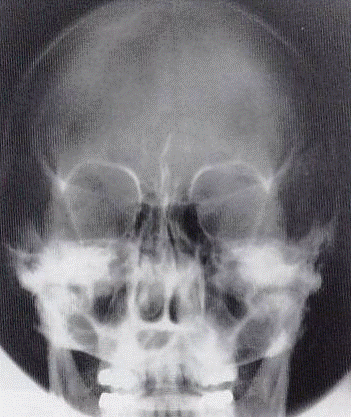

Demonstrated Pathology

Fractures and alterations of facial bones:

Visible Anatomical Structures

Symmetric orbits, clear frontal sinuses, no rotation.

Caldwell vs Waters

CALDWELL

Angulation: 15° caudal

Exit point: Nasion

Best visualizes: Frontal sinuses, orbits